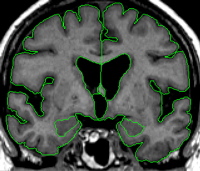

Segmentation: Amygdala

| General Description The amygdala is located in the medial temporal lobe. It has a rounded shape and is situated anterior and superior to the hippocampus. Anteriorly, the amygdala borders the entorhinal/perirhinal temporopolar cortex. Superiorly, it borders the basal forebrain and the choroidal fissure. Medially, the amygdala borders the entorhinal cortex (in its anterior most tip) as well as the subarachnoid CSF of the medial temporal surface. Its lateral borders are the temporal horn of the lateral ventricle as well as (more rostrally) the white matter core of the temporal pole. Inferiorly, it borders with the entorhinal cortex (PHa), and more posteriorly, the hippocampus. Its caudal border is the hippocampus. | |

|  | Part II - Medial portion of the amygdala As you move posteriorly, the amygdala becomes easier to visualize. Use a contour line to give the general outline of the amygdala, then check the other views available to you to confirm this outline. When the amygdala is in its full extent, it is fairly easy to see in the coronal view. Remember that the amygdala has a very small wave that crests over the choroidal fissure. Refer to an atlas to see this wave more clearly. Alter the brightness of the screen so that you can adequately see the strip of white matter that separates the amygdala from the cortical areas. |